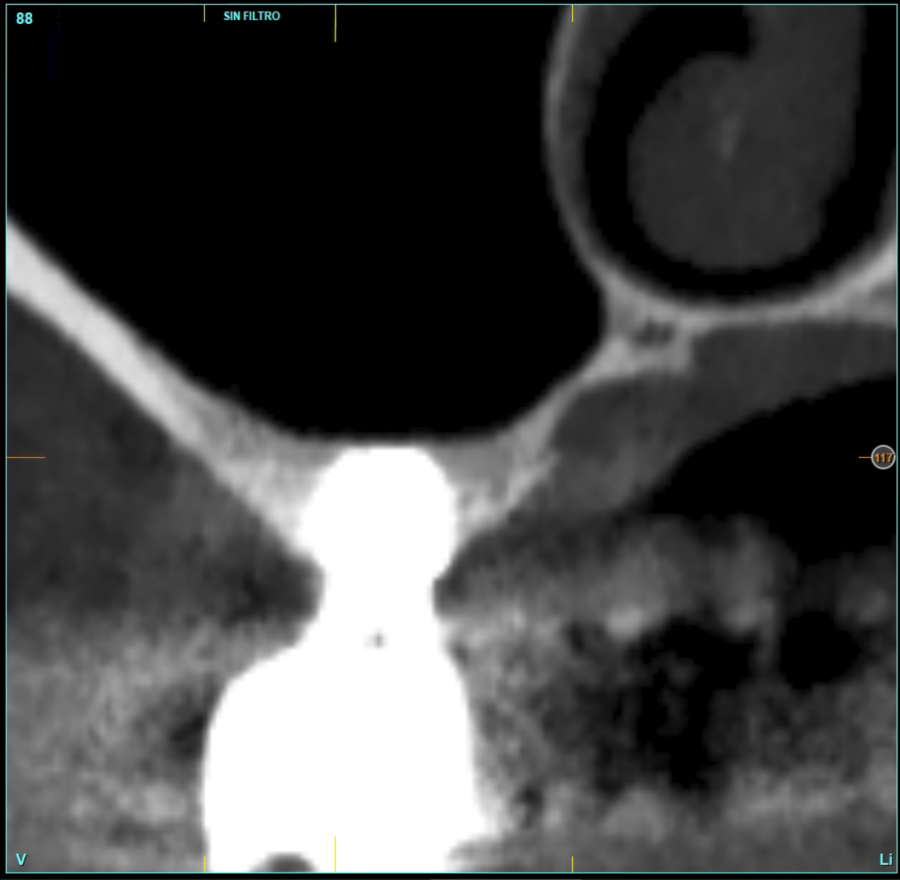

In all cases, a diagnosis was made based on study models, intraoral examination of the patient and performing a Cone-beam analysed using the specific BTI-Scan 3 software (Biotechnology Institute, Vitoria, Alava, Spain).

Patients attend subsequent check-ups performing a control Cone-Beam after 5 months (before loading the implant) and after one year of the load, performing a new measurement in these images to analyse the bone gain and the maintenance of the same. In these check-ups, data are collected on prosthetic complications or crestal bone loss in these patients, as well as possible failures.

Figures 2-19 show one of the cases included in the study.